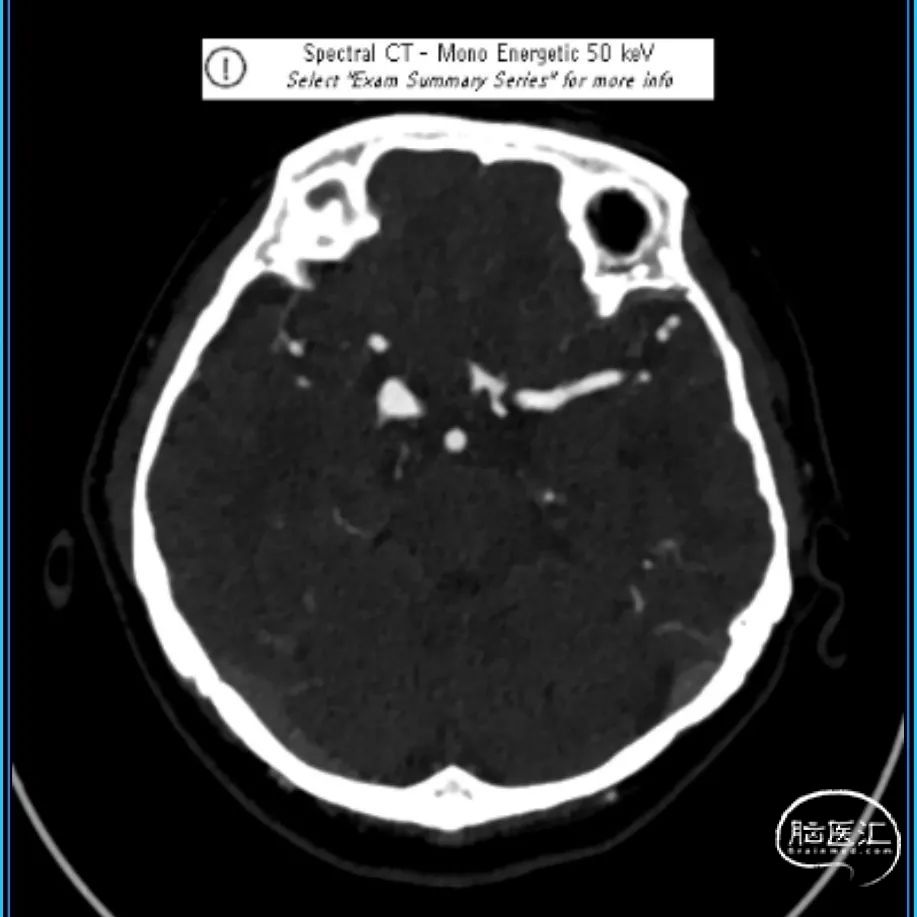

术后CTA:

麻醉复苏顺利,术后患者神志清楚,对答切题,双侧瞳孔等大等圆,四肢肌力正常,无新发功能障碍,继续口服双抗血小板(阿司匹林+替格瑞洛)治疗。

术后定期随访情况,术后4天出院,等待半年及1年复查随访。